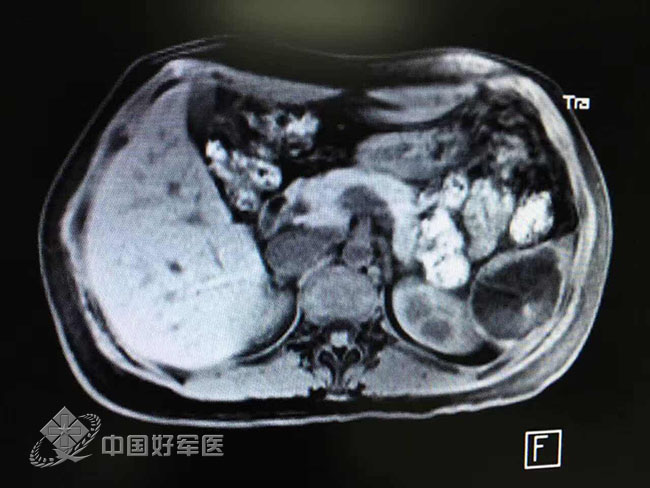

“取出胎兒時(shí),他已有兩到三個(gè)月的胎兒差不多大小,約5.4X4.5X3.9CM大?!崩罱▊フf,這個(gè)胎兒有頑強(qiáng)生命力,已明顯長出頭、臉、鼻、眼睛、四肢等。